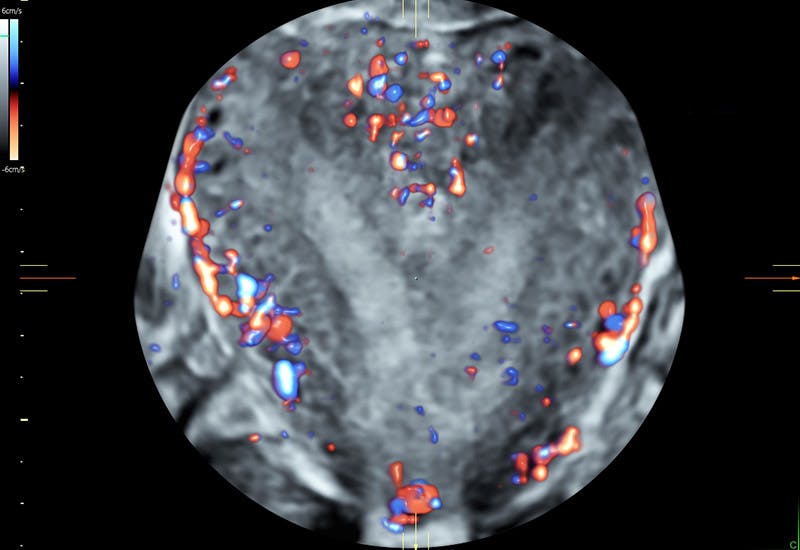

Highly sensitive color Doppler is needed to detect presence of bloodflow within the endometrium.

3D Glass Body aids in the location of blood vessels for surgical planning.